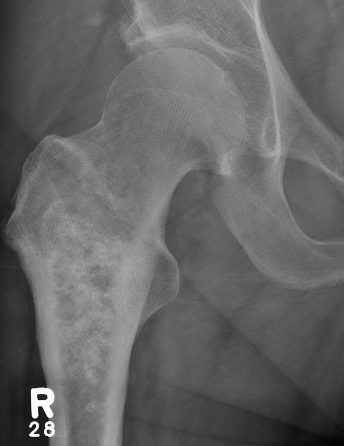

X-ray

Lytic lesion with punctate or spotty calcification

Worrisome features

- growth over time

- large > 5cm

- endosteal scalloping is hallmark of chondrosarcoma

Enchondroma enlarging over time

Large calcification with endosteal scalloping humerus

Large calcified lesion with endosteal scalloping

Pathological fracture